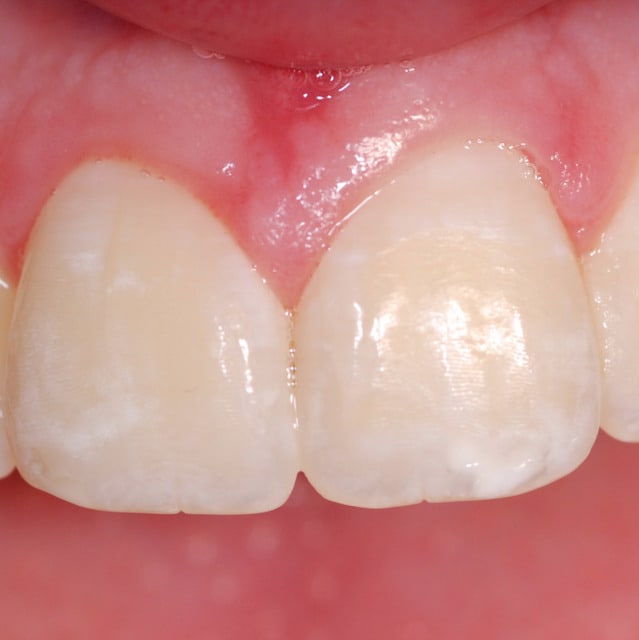

Rien a voir, mais j'aime bien la photo 3, p-emmanuel.

Pour un futur projet consacré a l'analyse en ligne des teintes (peut etre l'année prochaine), ta photo va peut etre me servir de reference; j'aimerais savoir quelle est la teinte que tu obtiens (vita ou vita3D) au 1/3 median de 21.

Moi je la trouve pas mal ta photo 3.

Le défaut du flash LED c'est la dominante bleu/désaturé des couleurs mais c'est correct je trouve.

Tiens une photo pas séchée non plus, avec mon capteur sale. Faite au 1:1 il me semble, avec flash annulaire Canon. Moins de reflets mais il y en a quand même.

Le but du flash annulaire c'est de supprimer les ombres portées, du coup on a un risque de reflet sur les surfaces réfléchissantes.